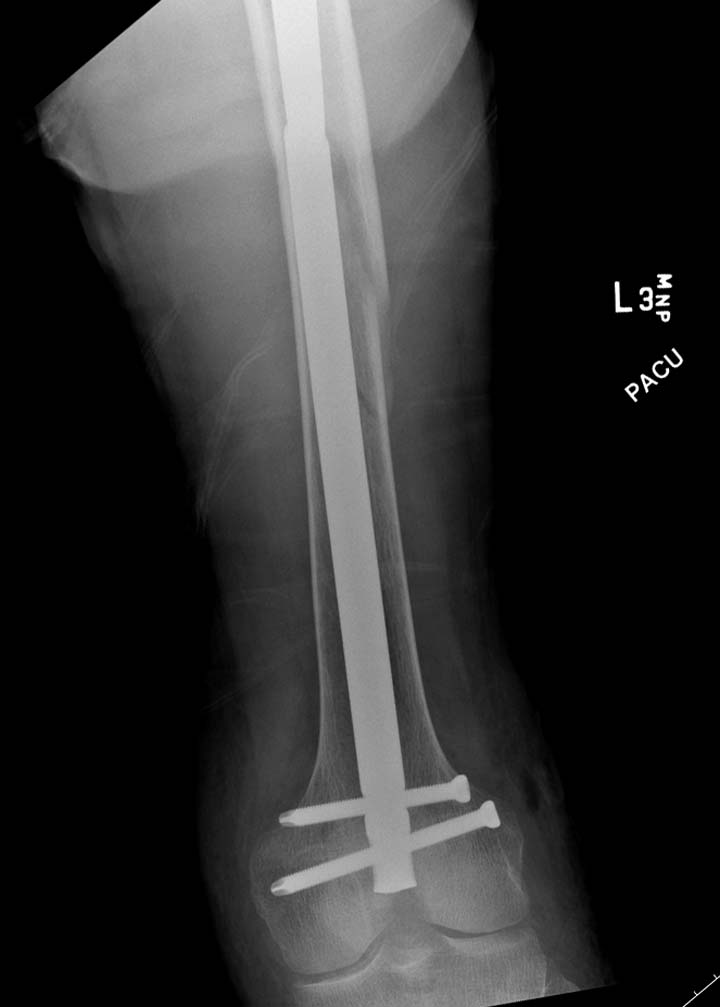

остаться до конца лечения, начал изучать язык... Для облегчения

транспортировки на второй день после поступления правая сторона была

фиксирована ретроградным гвоздем.

Теперь по серьезному. Учитывая качество кости и низкий гемоглобин,

периодический гемодиализ и воодушевленный результатом выступлении

Челнокова, вместо пластины решил попробовать гвоздь. Но жесткие FDА

условии не позволяют воспользоваться дивайсом до получения разрешения на

пользование.

Гвоздь из ретроградного гвоздя DePuy в 15 мм получился немного тоньше,

чем у Российских коллег.

Операция не обошлась без казуса, при подготовке гвоздя произошла ошибка

в расчете. Пришлось коррегигировать по ходу операции, где длинный

дистальный отдел гвоздя срезали во время операции.

А так вроде первый американский опыт прошел удачно. У больного низкий

гемоглобин, который подправили во время операции переливанием крови.

надеюсь, контрагированные мышцы сохранит длину конечности. Контрольный

снимок показал устойчивую фиксацию.